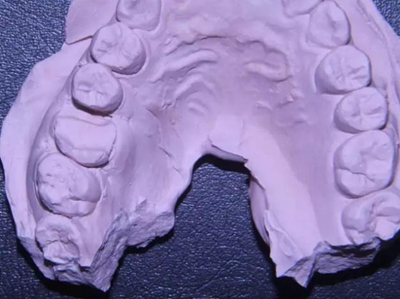

改良垂直褥式縫合關(guān)閉傷口,傷口無(wú)明顯滲血,高嵌體預(yù)備完畢后,硅橡膠取模,見邊緣清晰。灌注模型,模型上3MZ350XT分層堆塑高嵌體。

硅橡膠取模后,灌注模型,科爾琥珀樹脂制作嵌體。